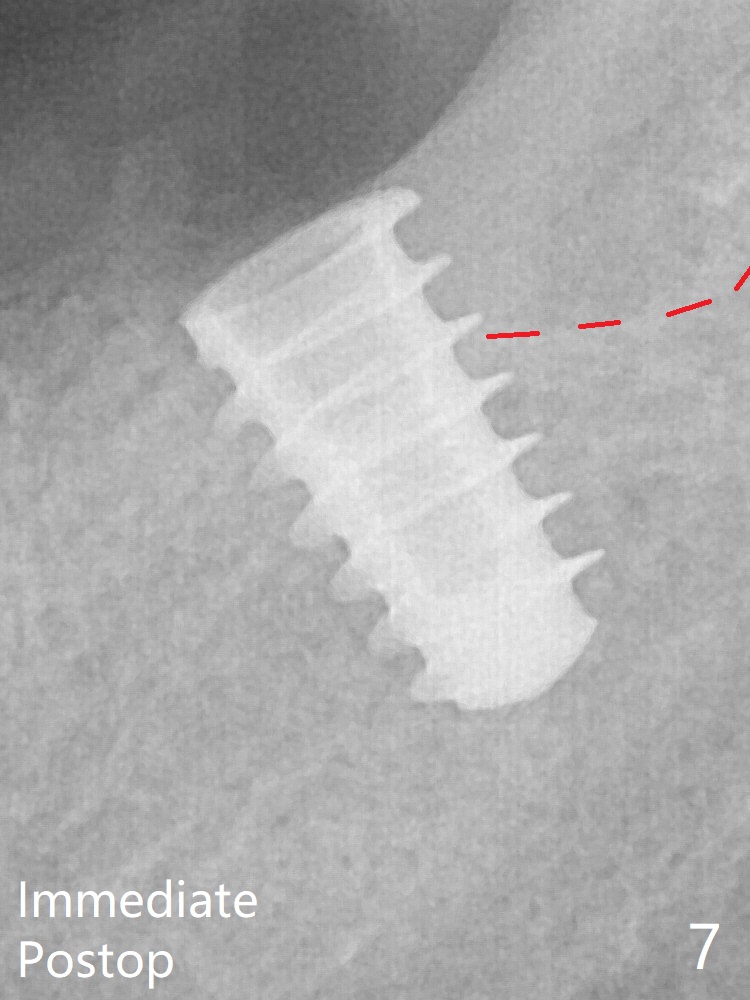

After increase in osteotomy depth for 1-2 mm with MD 4.3 mm, the 5.5x9 mm implant barely obtains stability (~ 10 Ncm, Fig.7). Healing screw is placed. Osteogen plug is inserted in the distal portion of the socket; autogenous bone around the implant and Collagen plug to close the socket opening. Last suture and periodontal dressing are applied.

In fact the distal coronal threads of the implant are exposed due to socket morphology (Fig.2 yellow dashed line, Fig.7 red dashed line). Bone graft should be securely placed immediately distal to the implant to prevent periimplantitis. The implant plateau is covered by the bone 2 years 9 months postop (Fig.8 *).